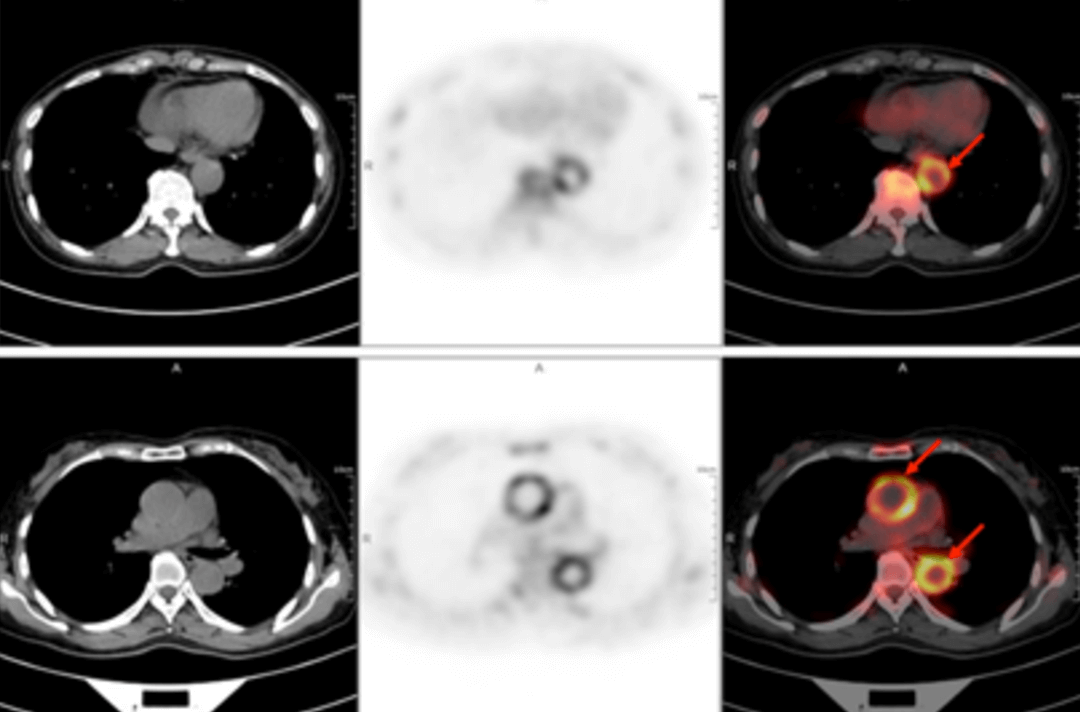

58-letnia kobieta trafiła do szpitala z powodu gorączki trwającej z przerwami od ponad 40 dni. Najwyższa zmierzona temperatura ciała wynosiła 38,9℃. Inne objawy obejmowały zmęczenie i ból stawów barkowych szczególnie nasilony po południu oraz nocą, dreszcze, krwioplucie, ból i ucisk w klatce piersiowej oraz duszności. Po dwóch tygodniach dożylnego podawania antybiotyków cefalosporynowych nie było poprawy, a gorączka się utrzymywała. W poradniach odnotowywano u pacjentki „gorączkę nieznanego pochodzenia”. W badaniu przedmiotowym nie znaleziono ewidentnych wskazówek pozwalających na diagnozę. Wyniki rutynowego badania krwi były następujące: wskaźnik sedymentacji erytrocytów w pierwszej godzinie – 72 mm; białko C-reaktywne o wysokiej czułości: 204,20 mg/l. Następnie u chorej wykonano badanie PET/TK całego ciała z zastosowaniem znacznika F-FDG (fluorodeoksyglukozy) w celu znalezienia przyczyny gorączki nieznanego pochodzenia.

W obrazach PET/TK w kilku lokalizacjach (obustronna tętnica szyjna wewnętrzna, tętnica szyjna wspólna, pień ramienno-głowowy, obustronne tętnice podobojczykowe i pachowe, aorta piersiowa, aorta brzuszna, obustronna tętnica biodrowa wspólna, tętnica biodrowa wewnętrzna, tętnica biodrowa zewnętrzna i tętnica udowa) wystąpiło pogrubienie ściany ze zwiększonym metabolizmem glukozy, co uznano za spowodowane zmianami zapalnymi. Na podstawie wywiadu lekarskiego, objawów klinicznych, badania i wyników badań obrazowych u pacjentki rozpoznano zespół Takayasu. Po zastosowaniu standardowego leczenia przeciwzapalnego temperatura ciała spadła, a stan pacjentki uległ poprawie.